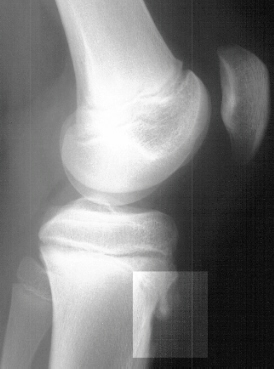

This patient is a 12 year old male who initially presented

with a history of left knee pain for 4 months. He denied any obvious

history of trauma. He claimed to play a lot of basketball and

felt that the pain was worse after playing. The patient also claimed

to have a "knot" over the anterior aspect of his proximal

tibia. On physical examination the patient had a prominent tibial

tubercle which was warm, swollen, and tender. The knee did not

have an effusion, and there was no joint line tenderness. There

was also no tenderness over the patellar tendon. There was full

range of motion in the knee, but the patient had hamstring tightness.

He also had pain with resisted knee extension. There was no instability

to varus or valgus stress. McMurray test was negative. Lachman

test was negative. Patellar tracking was normal, and there was

no pain with loading of the patellofemoral joint. X-ray of the

left knee revealed an ossicle anterior to the tibial tuberosity.